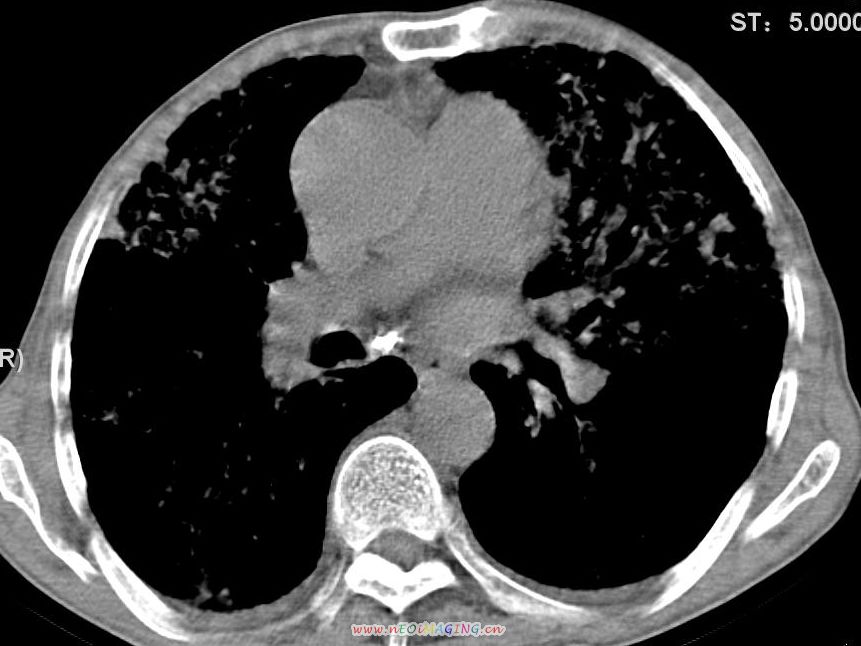

患者咳嗽月余,高热数天,咳黄色稍脓痰。

高热数天,咳黄色稍脓痰,肯定应该有急性化脓性感染,左上叶舌段及右肿叶可见多量斑片状及支气管气像,首先考虑肺部感染合并血型播散性肺脓肿(脓肿为早期改变),其次不排除有肺泡癌,第三不排除结核,建议治疗后复查

双肺野分布多个小结节状高密度影,其内散在斑片状模糊影,气管。支气管通畅,纵隔内淋巴结钙化,胸膜局限性增厚粘连,胸腔少量积液。结合病史考虑结核并感染的可能性大,胸膜炎并积液。肺泡癌待排。

纵隔内见钙化的淋巴节,上肺见钙化灶,双肺均匀弥漫分布小结节影,边缘较清楚,能不能考虑是在矽肺的基础上并发的结核和感染,请详细了解病史结合临床.

亚急性血行播散性肺结核可能性大伴少量胸腔积液,建议进一步检查。